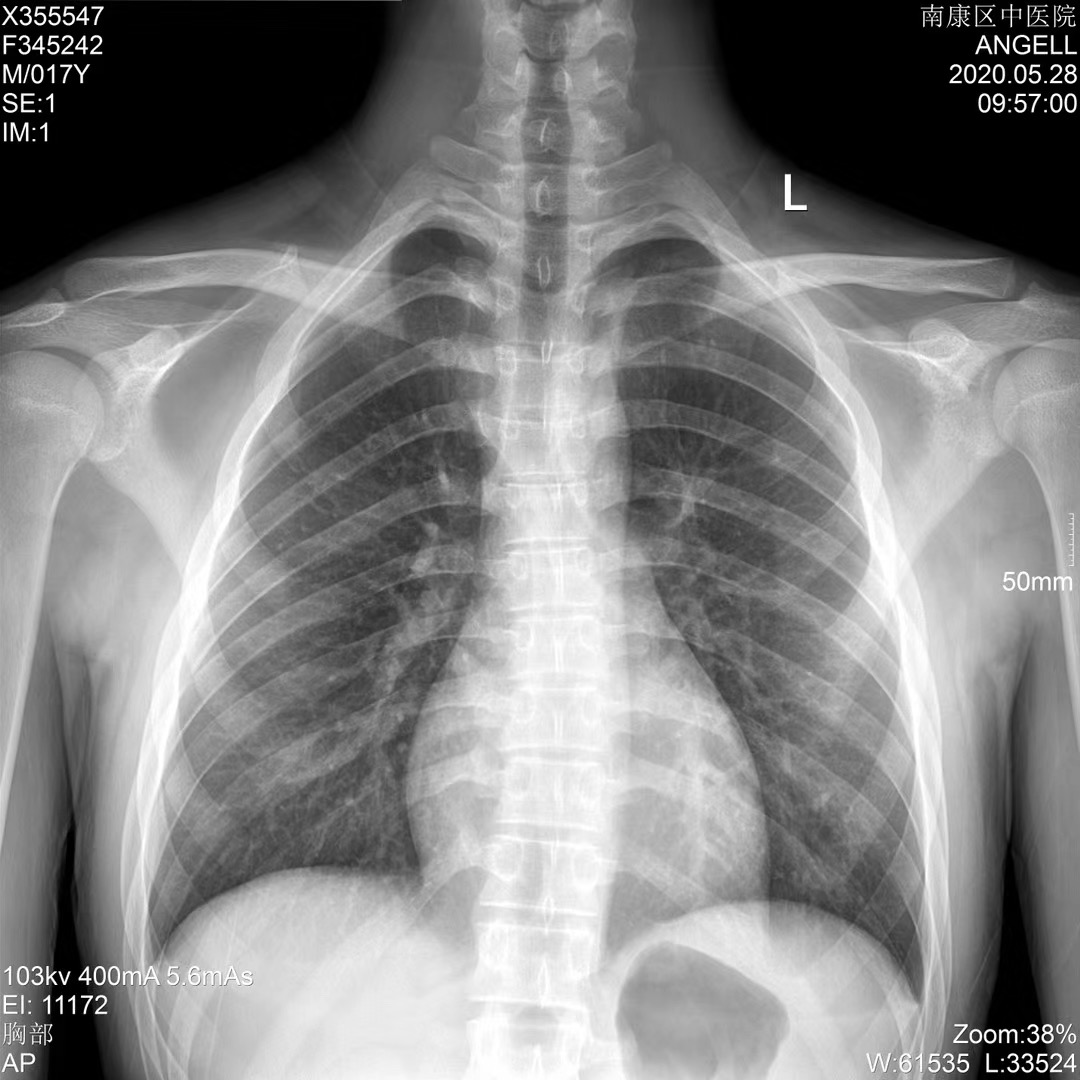

Medical Film

Medical Dry Film has image layer and protect layer on different side of bluish polyester bases, and there are no sensitive silver halide in both layer.The film is fit for thermal printer to print digital image which is processed and stored in the computer, to attain the enhanced x-ray image quality.¥ 0.00Buy now